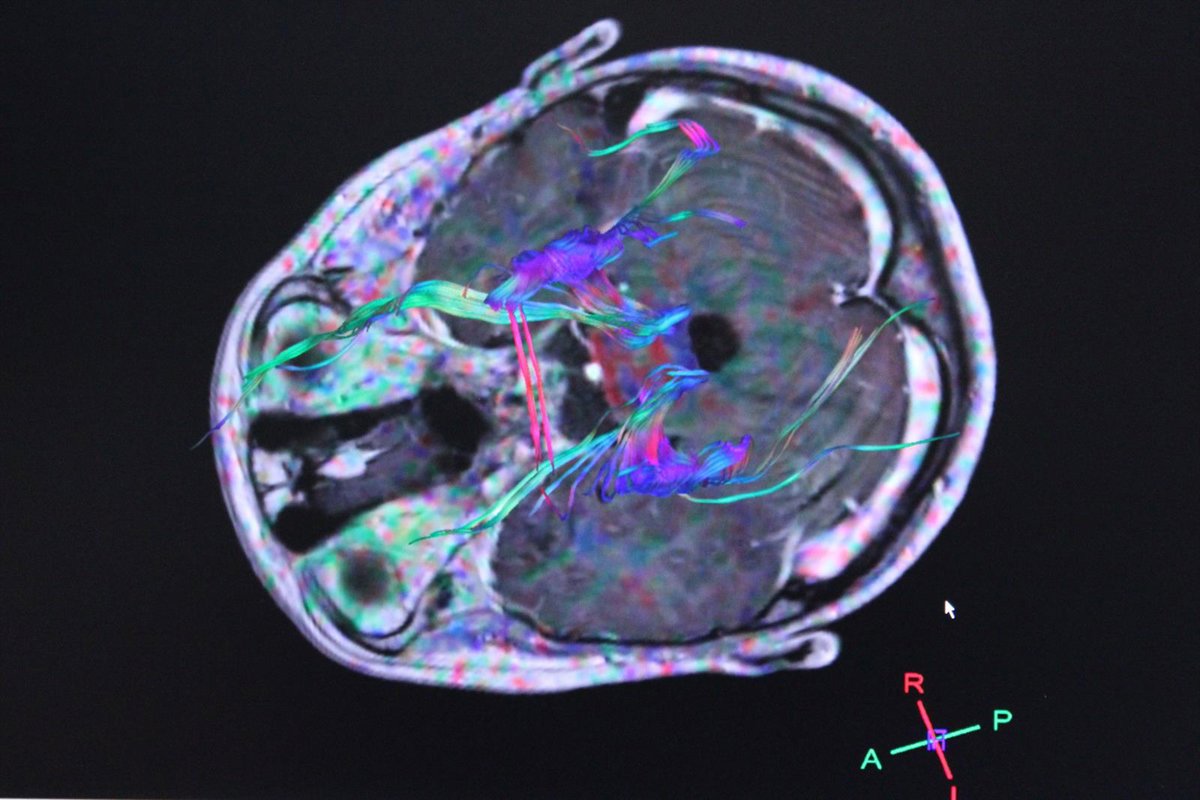

Archivo - Imagen de archivo de actividad del cerebro

Archivo - Imagen de archivo de actividad del cerebro - EUROPA PRESS - Archivo